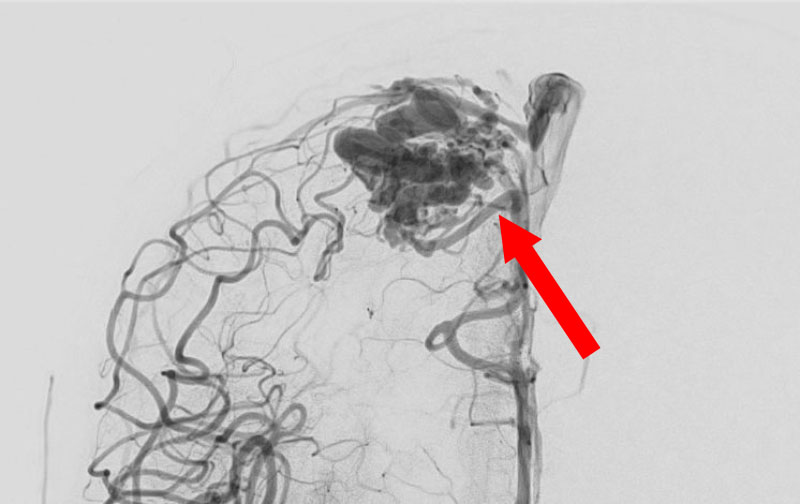

1585

'25年10月6日

脳動静脈奇形

50代

大阪府の病院

手術写真

治療

前

中

後